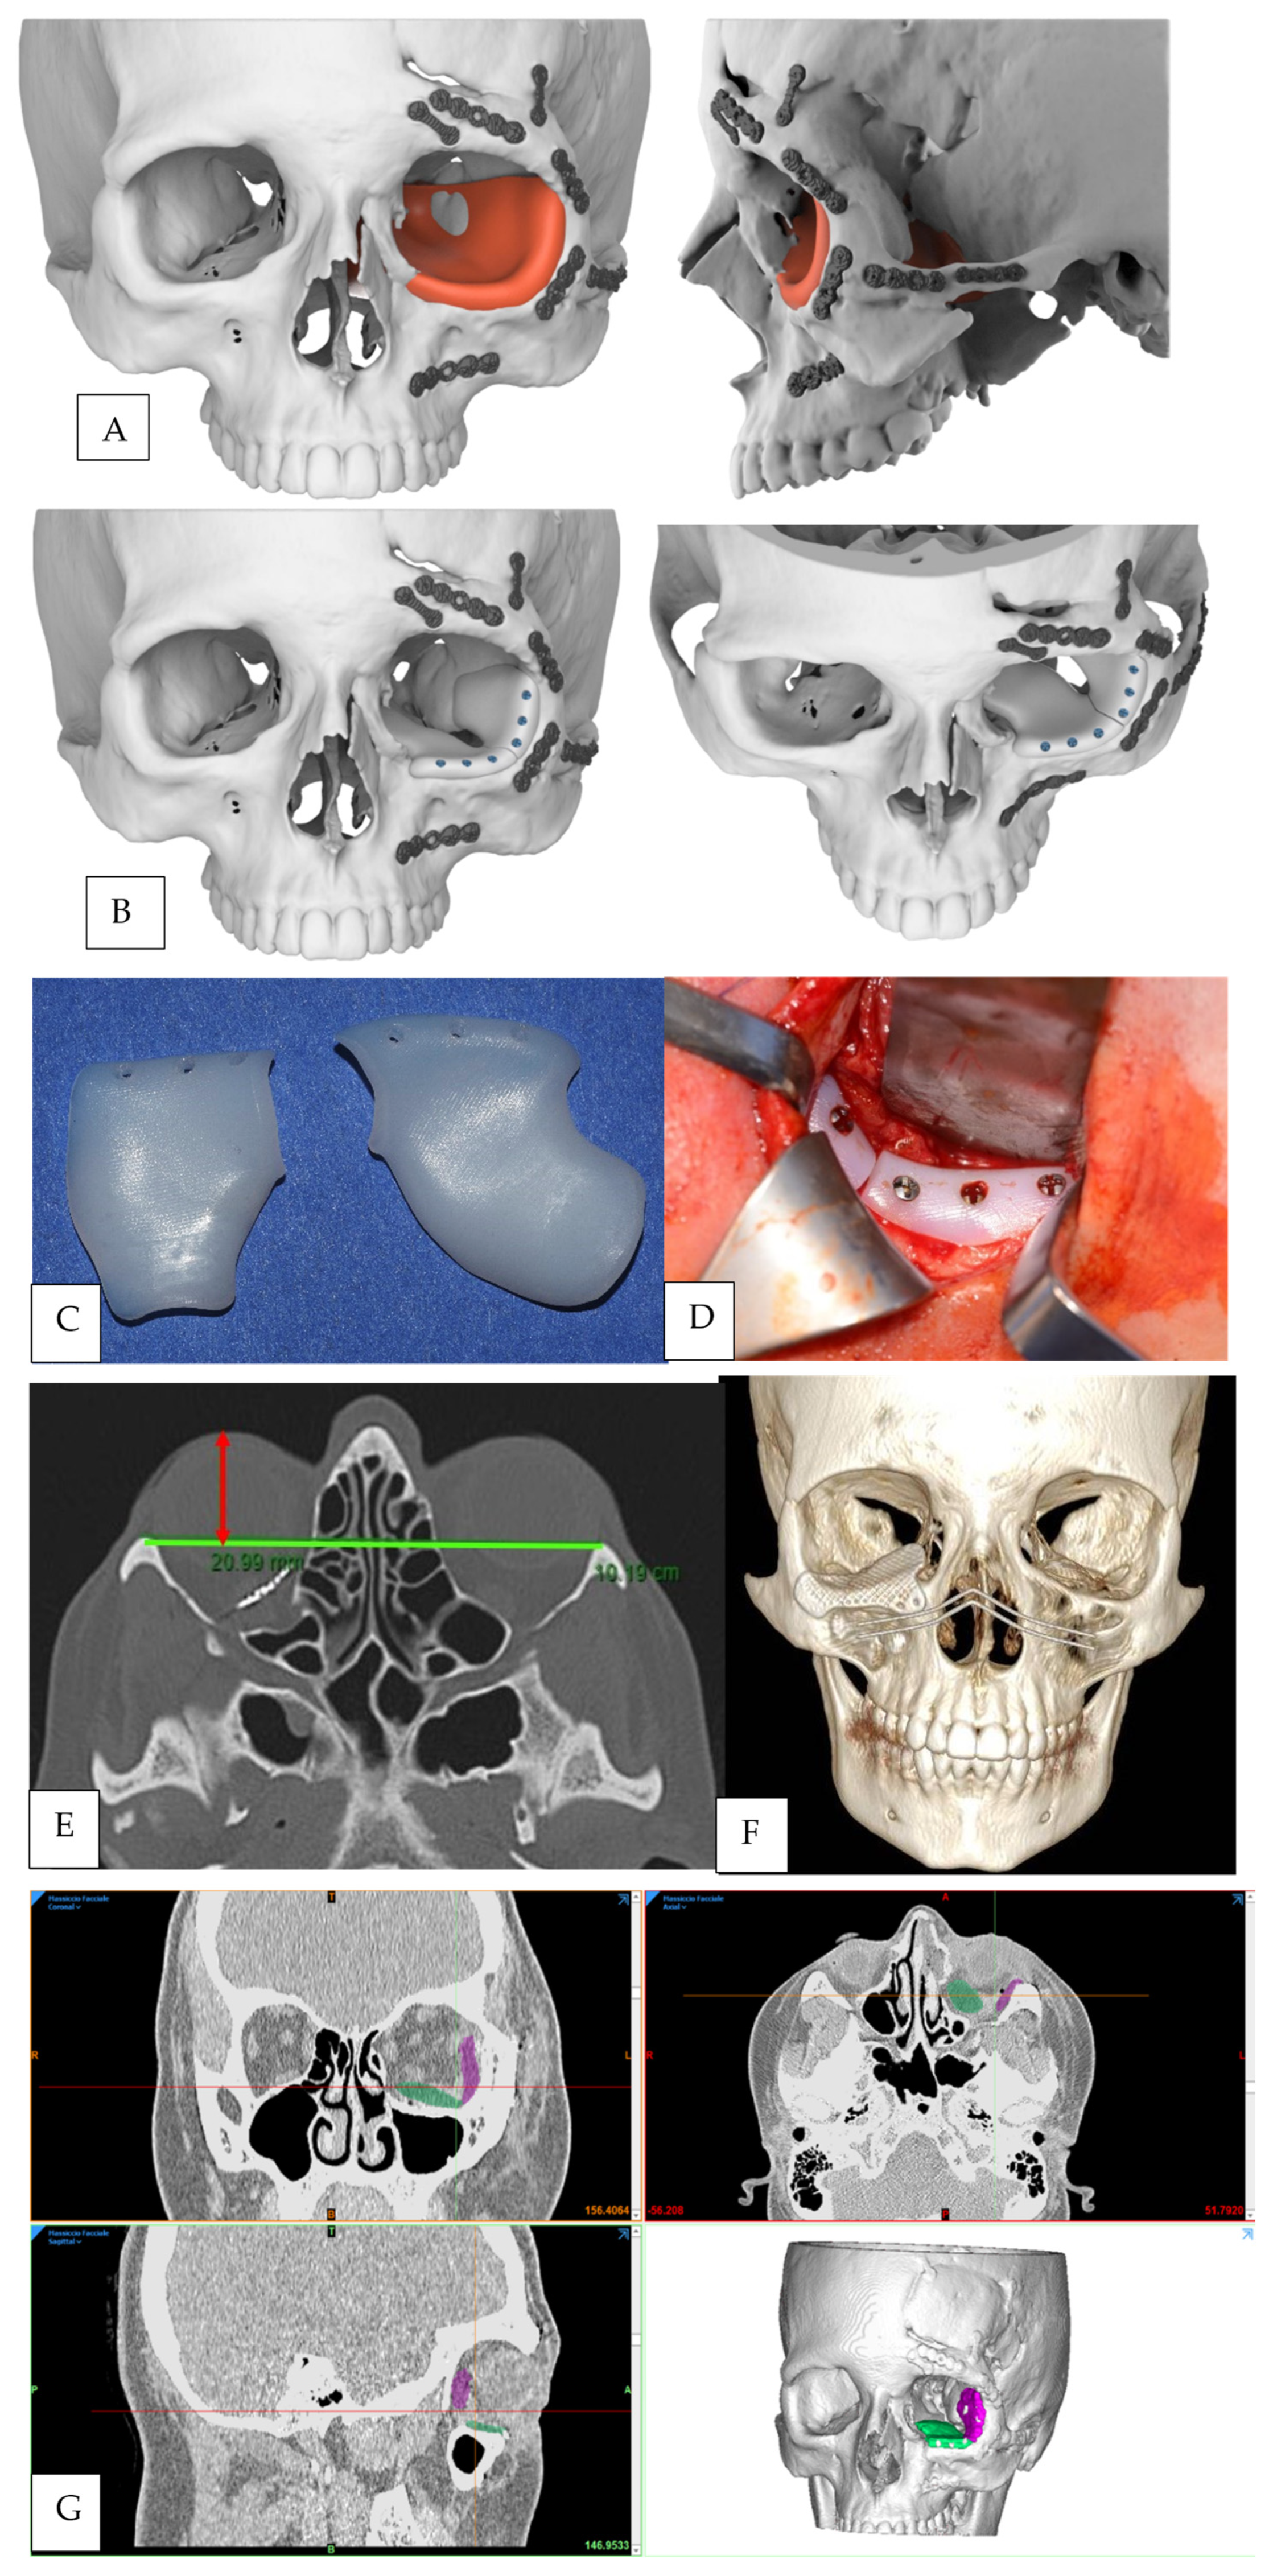

The CT scan was evaluated, and the normal uninjured side of the craniofacial skeleton was reflected onto the contralateral injured side by a mirroring technique using Geomagic Freeform 2016 (3D Systems, Rock Hill, SC, USA) (Figure 1A). A reconstructive orbital floor implant was then designed virtually on the mirrored orbital bone surface (Figure 1B).

Figure 1.

(A) Mirroring of the healthy bone surface on the affected side using 3D reconstruction of the CT scan. (B) CAD of the reconstructive left orbital floor implant. (C) High-density polyethylene implant in two pieces. (D) intraoperative image showing left orbital floor reconstruction via a transconjunctival approach through HDPE implant insertion. (E) Technique of proptosis measurement with CT as proposed by Ramli [18]. (F) Postoperative three-dimensional CT scan showing right orbital floor reconstruction using a customized titanium mesh. (G) 3D segmentation of the postoperative CT scan showing positioning of the HDPE implant with two different colors indicating each component of the prosthesis (green: medial component of the implant, purple: lateral component of the implant).

Nonporous high-density polyethylene (HDPE) implants were used in 2 patients (Figure 1C).

Preoperative and postoperative globe protrusions were assessed as described by Ramli et al. [18]. All patients underwent CT scans of the orbit after surgery (from 24 to 72 h after surgery). Each patient had their head strapped in the supine position during the scan to ensure reliability of the measurements. Their positions were centered by aligning the midsagittal line perpendicular to the laser line. The coronal line was centered 1 cm above the external auditory meatus.

An interzygomatic line was first drawn on the axial-view image in which the lens was best seen. A perpendicular line was then drawn from the inner corneal surface to the interzygomatic line, bisecting the lens. The length of this perpendicular line was taken as the primary measurement (Figure 1E). As proposed by Ramli [18], Hertel exophthalmometer and CT measurements of globe position are similar and strongly correlated.

Postoperative 3D CT scans were also evaluated to verify the correct positioning of the implant (Figure 1F).

For the two cases treated by positioning of HDPE implants, we performed a segmentation of postoperative CT scans in order to obtain information about the correct positioning of the implants, which cannot be easily detectable in a direct 3D reconstruction because of the radiolucent properties of HDPE (Figure 1G).